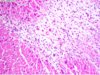

Organizing myocardial infarct

Micro:

1. after first few hours: intracellular edema, begining coagulative necrosis

2. after 12hrs: ongoing necrosis, pyknosis of nuclei, hypereosinophilia, neutrophils infiltration

3. 3‐7days: necrotic myocytes digested by invading macrophages

- *4.** 7‐10 days: growth of granulation tissue

- *5.**from 2 week: progressive synthes is of collagen and fibrosis